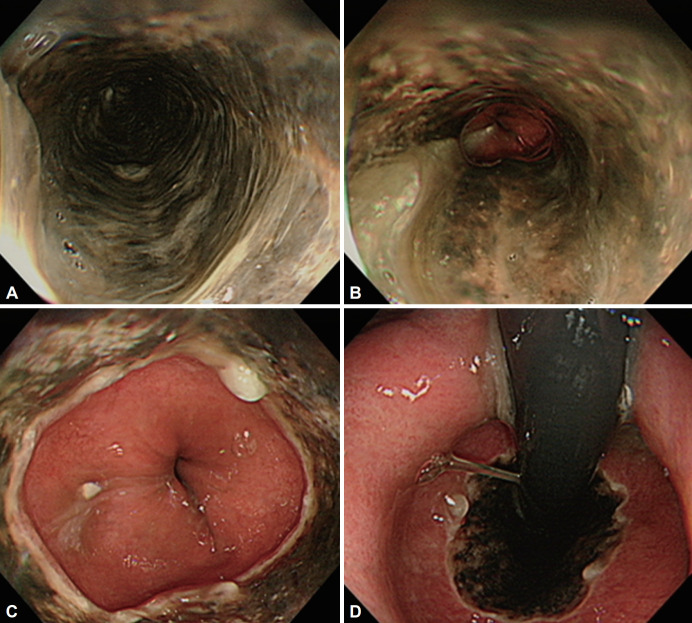

急性食管坏死(AEN),也被称为“黑色食管”,是一种罕见的临床疾病,其特征是食管内壁组织严重损伤和死亡。在内窥镜检查时,AEN通常呈现黑色外观。AEN的危险因素包括多器官功能障碍背景下的食管缺血、脓毒症、灌注不足、血管病变、创伤性胸主动脉横断、血栓栓塞现象、胃扭转、糖尿病酮症酸中毒、酒精中毒或恶性肿瘤。在此,我们报告一例以呼吸困难和糖尿病酮症酸中毒为表现的AEN病例,该患者以前未被诊断为糖尿病。

Acute esophageal necrosis (AEN), also known as "black esophagus," is a rare clinical condition marked by severe damage and death of the tissue lining the esophagus. During endoscopy, AEN typically presents with a blackened appearance. Risk factors for AEN include esophageal ischemia in the setting of multi-organ dysfunction, sepsis, hypoperfusion, vasculopathy, traumatic transection of the thoracic aorta, thromboembolic phenomena, gastric volvulus, diabetic ketoacidosis, alcohol intoxication, or malignancy. Here, we report a case of AEN diagnosed in a patient presenting with dyspnea and diabetic ketoacidosis who had not been diagnosed with diabetes mellitus previously.